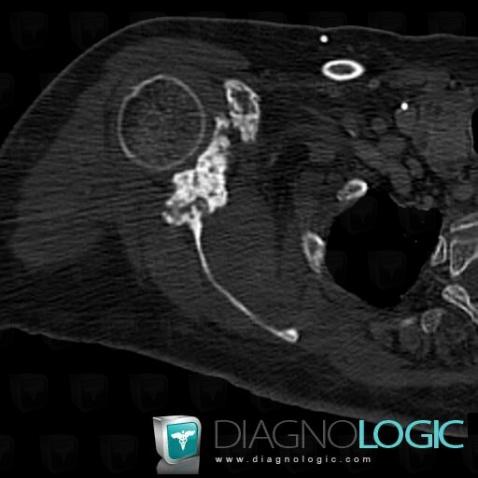

Metastasis, Scapula, CT

Here is the specific information in the key image above:

- Diagnosis Metastasis, Location(s) Scapula, with gamuts Solitary osteosclerotic bone lesion